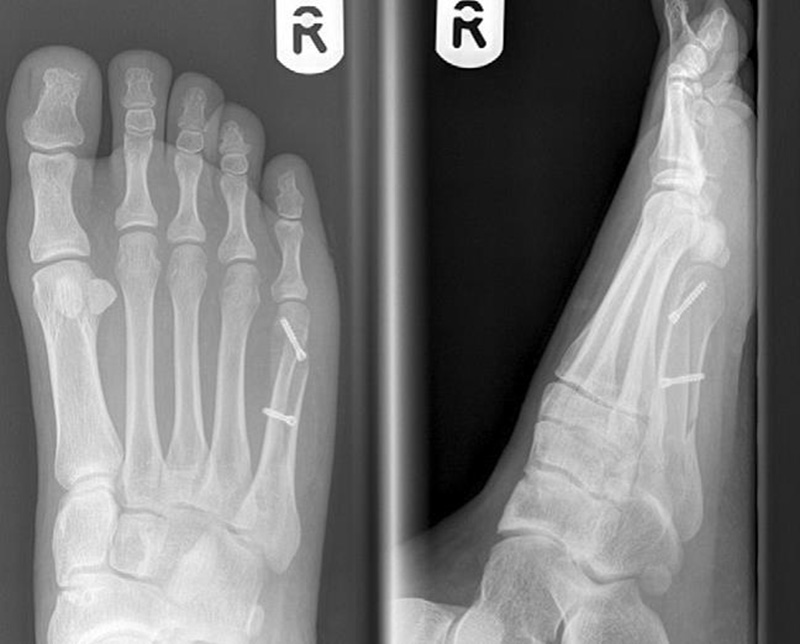

Abb. 3a, b: Präoperatives (a) und postoperatives (b) Röntgenbild bei Korrektur einer Typ I Deformität durch eine Exostosenabtragung.